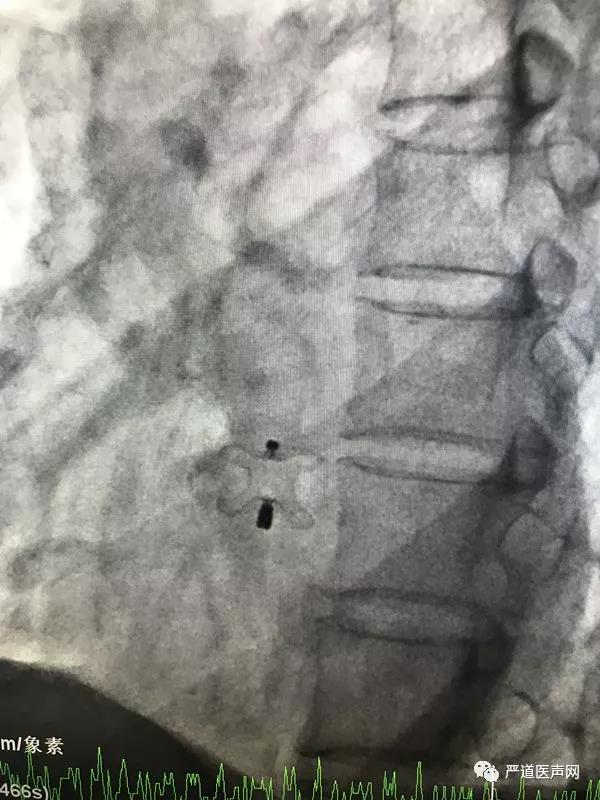

张玉顺教授与团队手术中

张玉顺教授分析认为:此例患者若使用以往的“动脉导管未闭封堵器”,必然会凸入下腔静脉较多,影响到下腔静脉血流,可能会造成封堵器内皮化延迟(人体自身心内膜的表层细胞向封堵器表面生长,形成一层内皮细胞的膜状组织,包裹封堵器。)甚至血栓栓塞等并发症;因为既往所使用动脉导管未闭封堵器边短腰 (经线) 长,而膜部室间隔封堵器边短腰短,置入后不会凸入下腔静脉,也就不会影响血流。根据这一思路, 9月14日在介入手术室、心脏超声的配合下,张玉顺教授的手术团队历经30分钟就十分顺利地完成了该例使用室缺封堵器封堵下腔型房间隔缺损手术。术后患者恢复良好,封堵器位置正常,无残余分流,将于近日出院。